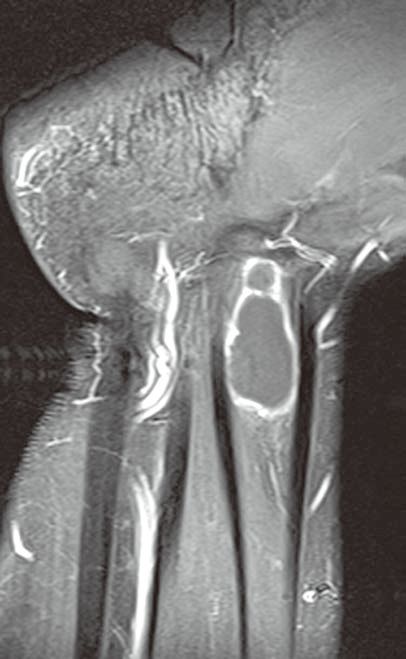

图1左腕手舟骨骨内腱鞘囊肿

A

B

C

D

左腕正位X线平片(A)示手舟骨远部骨内一小的透亮区。冠状位T1WI(B)示骨内病变呈低信号(箭)。冠状位(C)和横轴位(D)脂肪抑制T2WI示病变呈高信号,提示为液体(箭)